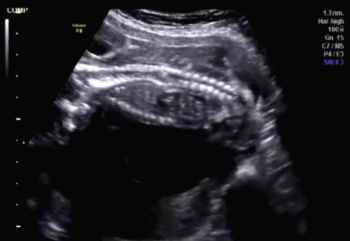

QUIZ: These images show something isn't quite right in a woman who is 34 weeks pregnant.